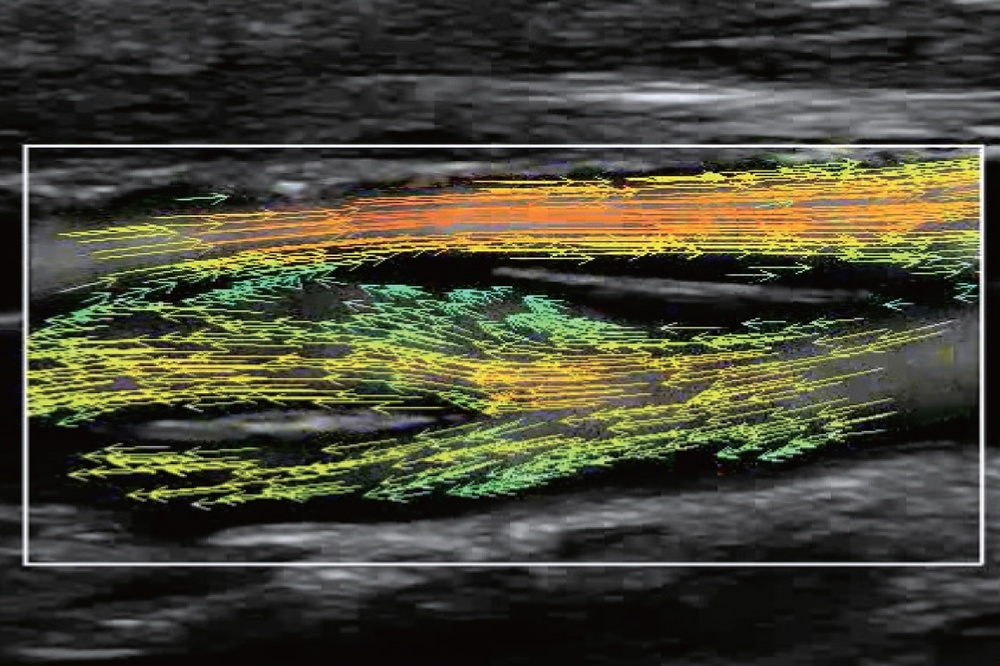

Метод визуализации интуитивно понятен и состоит из массива цветных стрелок, которые демонстрируют скорость и направление движения частиц крови.

На изображениях, приведенных ниже показаны примеры из клинической практики врачей ультразвуковой диагностики, полученные в процессе апробирования прибора Mindray Resona 7. Приводится наглядные примеры сравнения традиционного режима ЦДК и режима V Flow (Vector Flow).

Изображена яремная вена и бифуркация сонной артерии. CAA, ICA и ECA показаны на одном изображении. В режиме ЦДК отсутствует подробная гемодинамика. В режиме V Flow отображаются данные о скорости и направлении движения частиц крови во всей зоны интереса, включая изменения характеристик кровотока в сонной артерии и яремной вене.